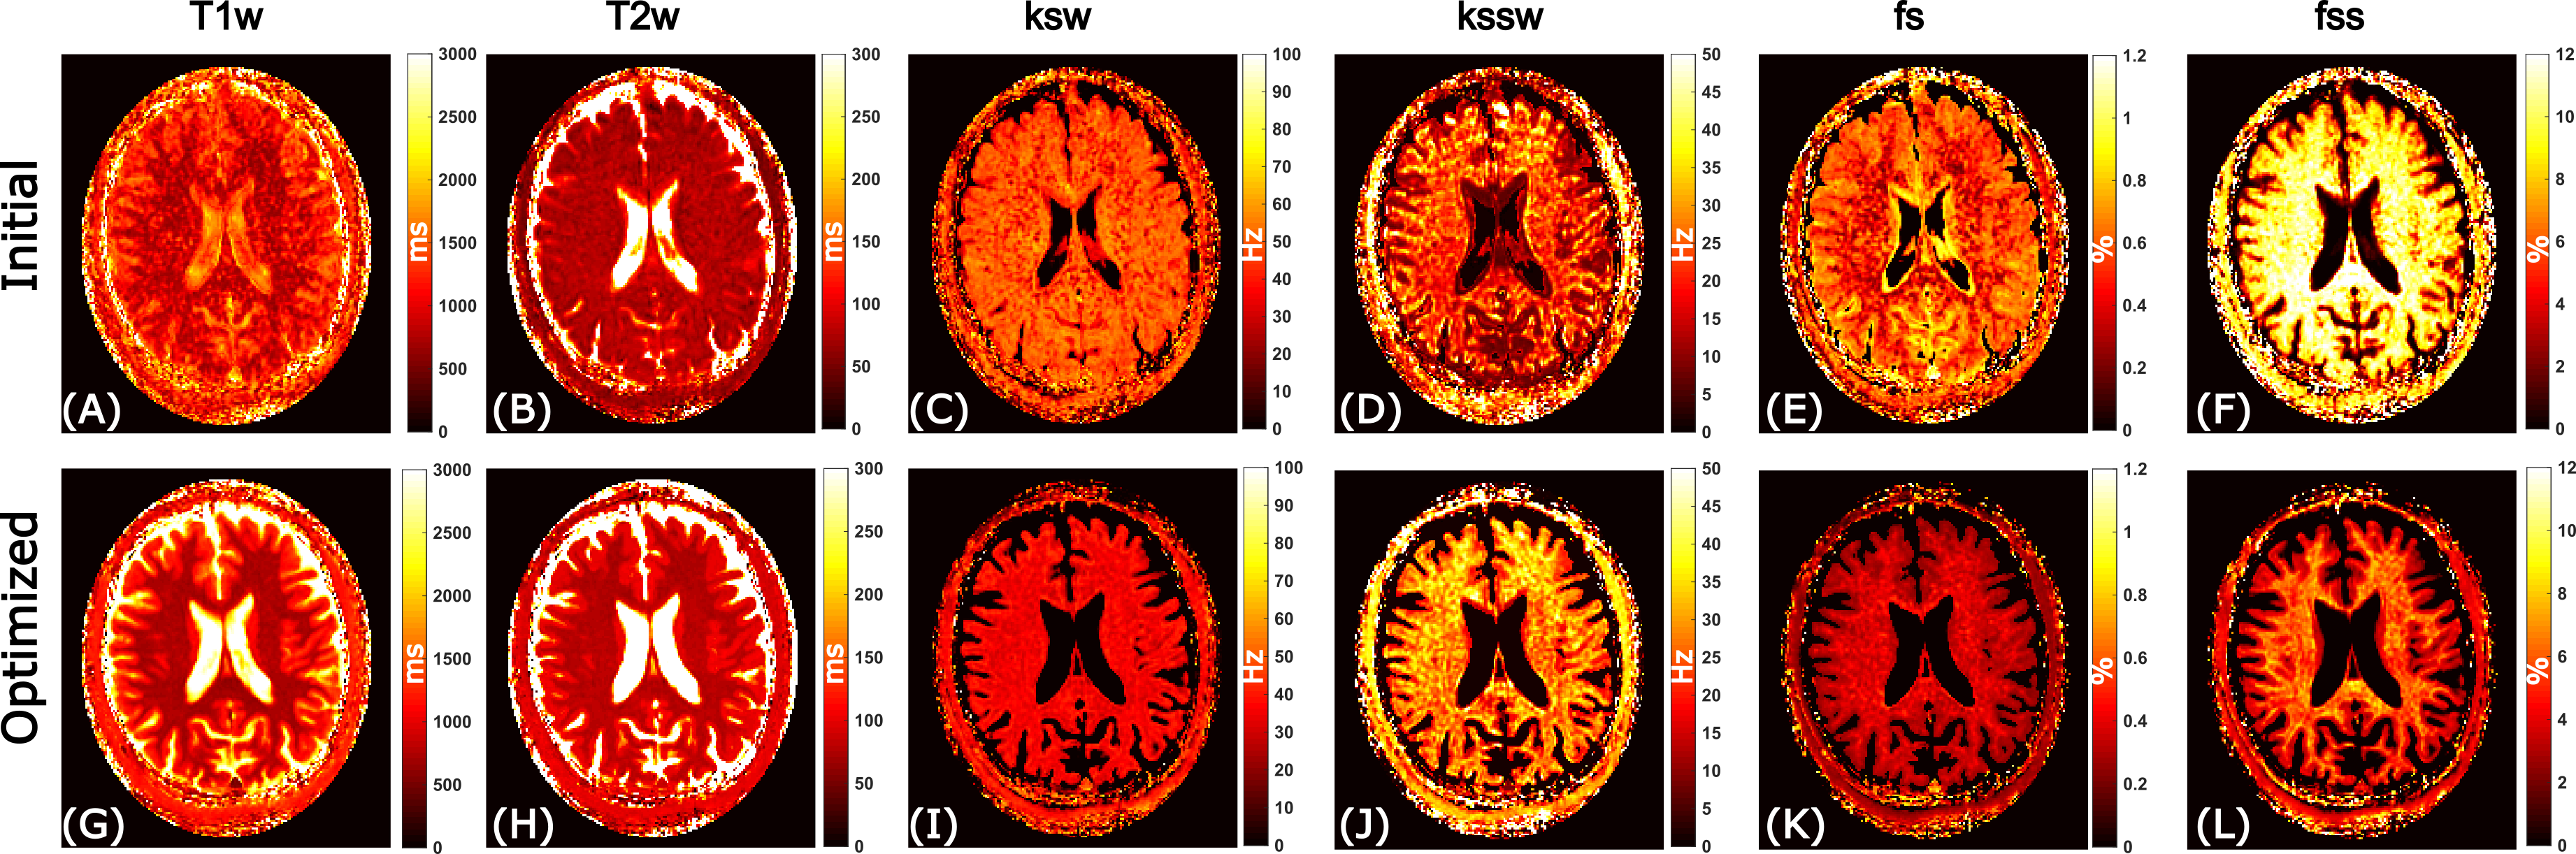

The initial and optimized schedules are shown in Figure 3. The optimized schedule resulted in a scan time that was 12% shorter than the initial random schedule (92 vs 105 seconds). The effect of SNR on the two schedules tested in the phantom is shown in Figure 4, where the optimized schedule provided a similar or lower error. In vivo CEST-MRF quantitative maps in the healthy subject are presented in Figure 5. Despite the 12% shorter acquisition time, the sequence with the optimized schedule presented tissue maps with improved image quality and good agreement to literature values [2].

Figure 5: Comparison of the initial and optimized schedules in a healthy subject in vivo. (A-F): Tissue maps reconstructed using the initial acquisition schedule. (G-L): Tissue maps reconstructed using the optimized acquisition schedule. Despite the 12% shorter acquisition time, the optimized sequence yielded tissue maps with improved image quality and good agreement to literature values [2].